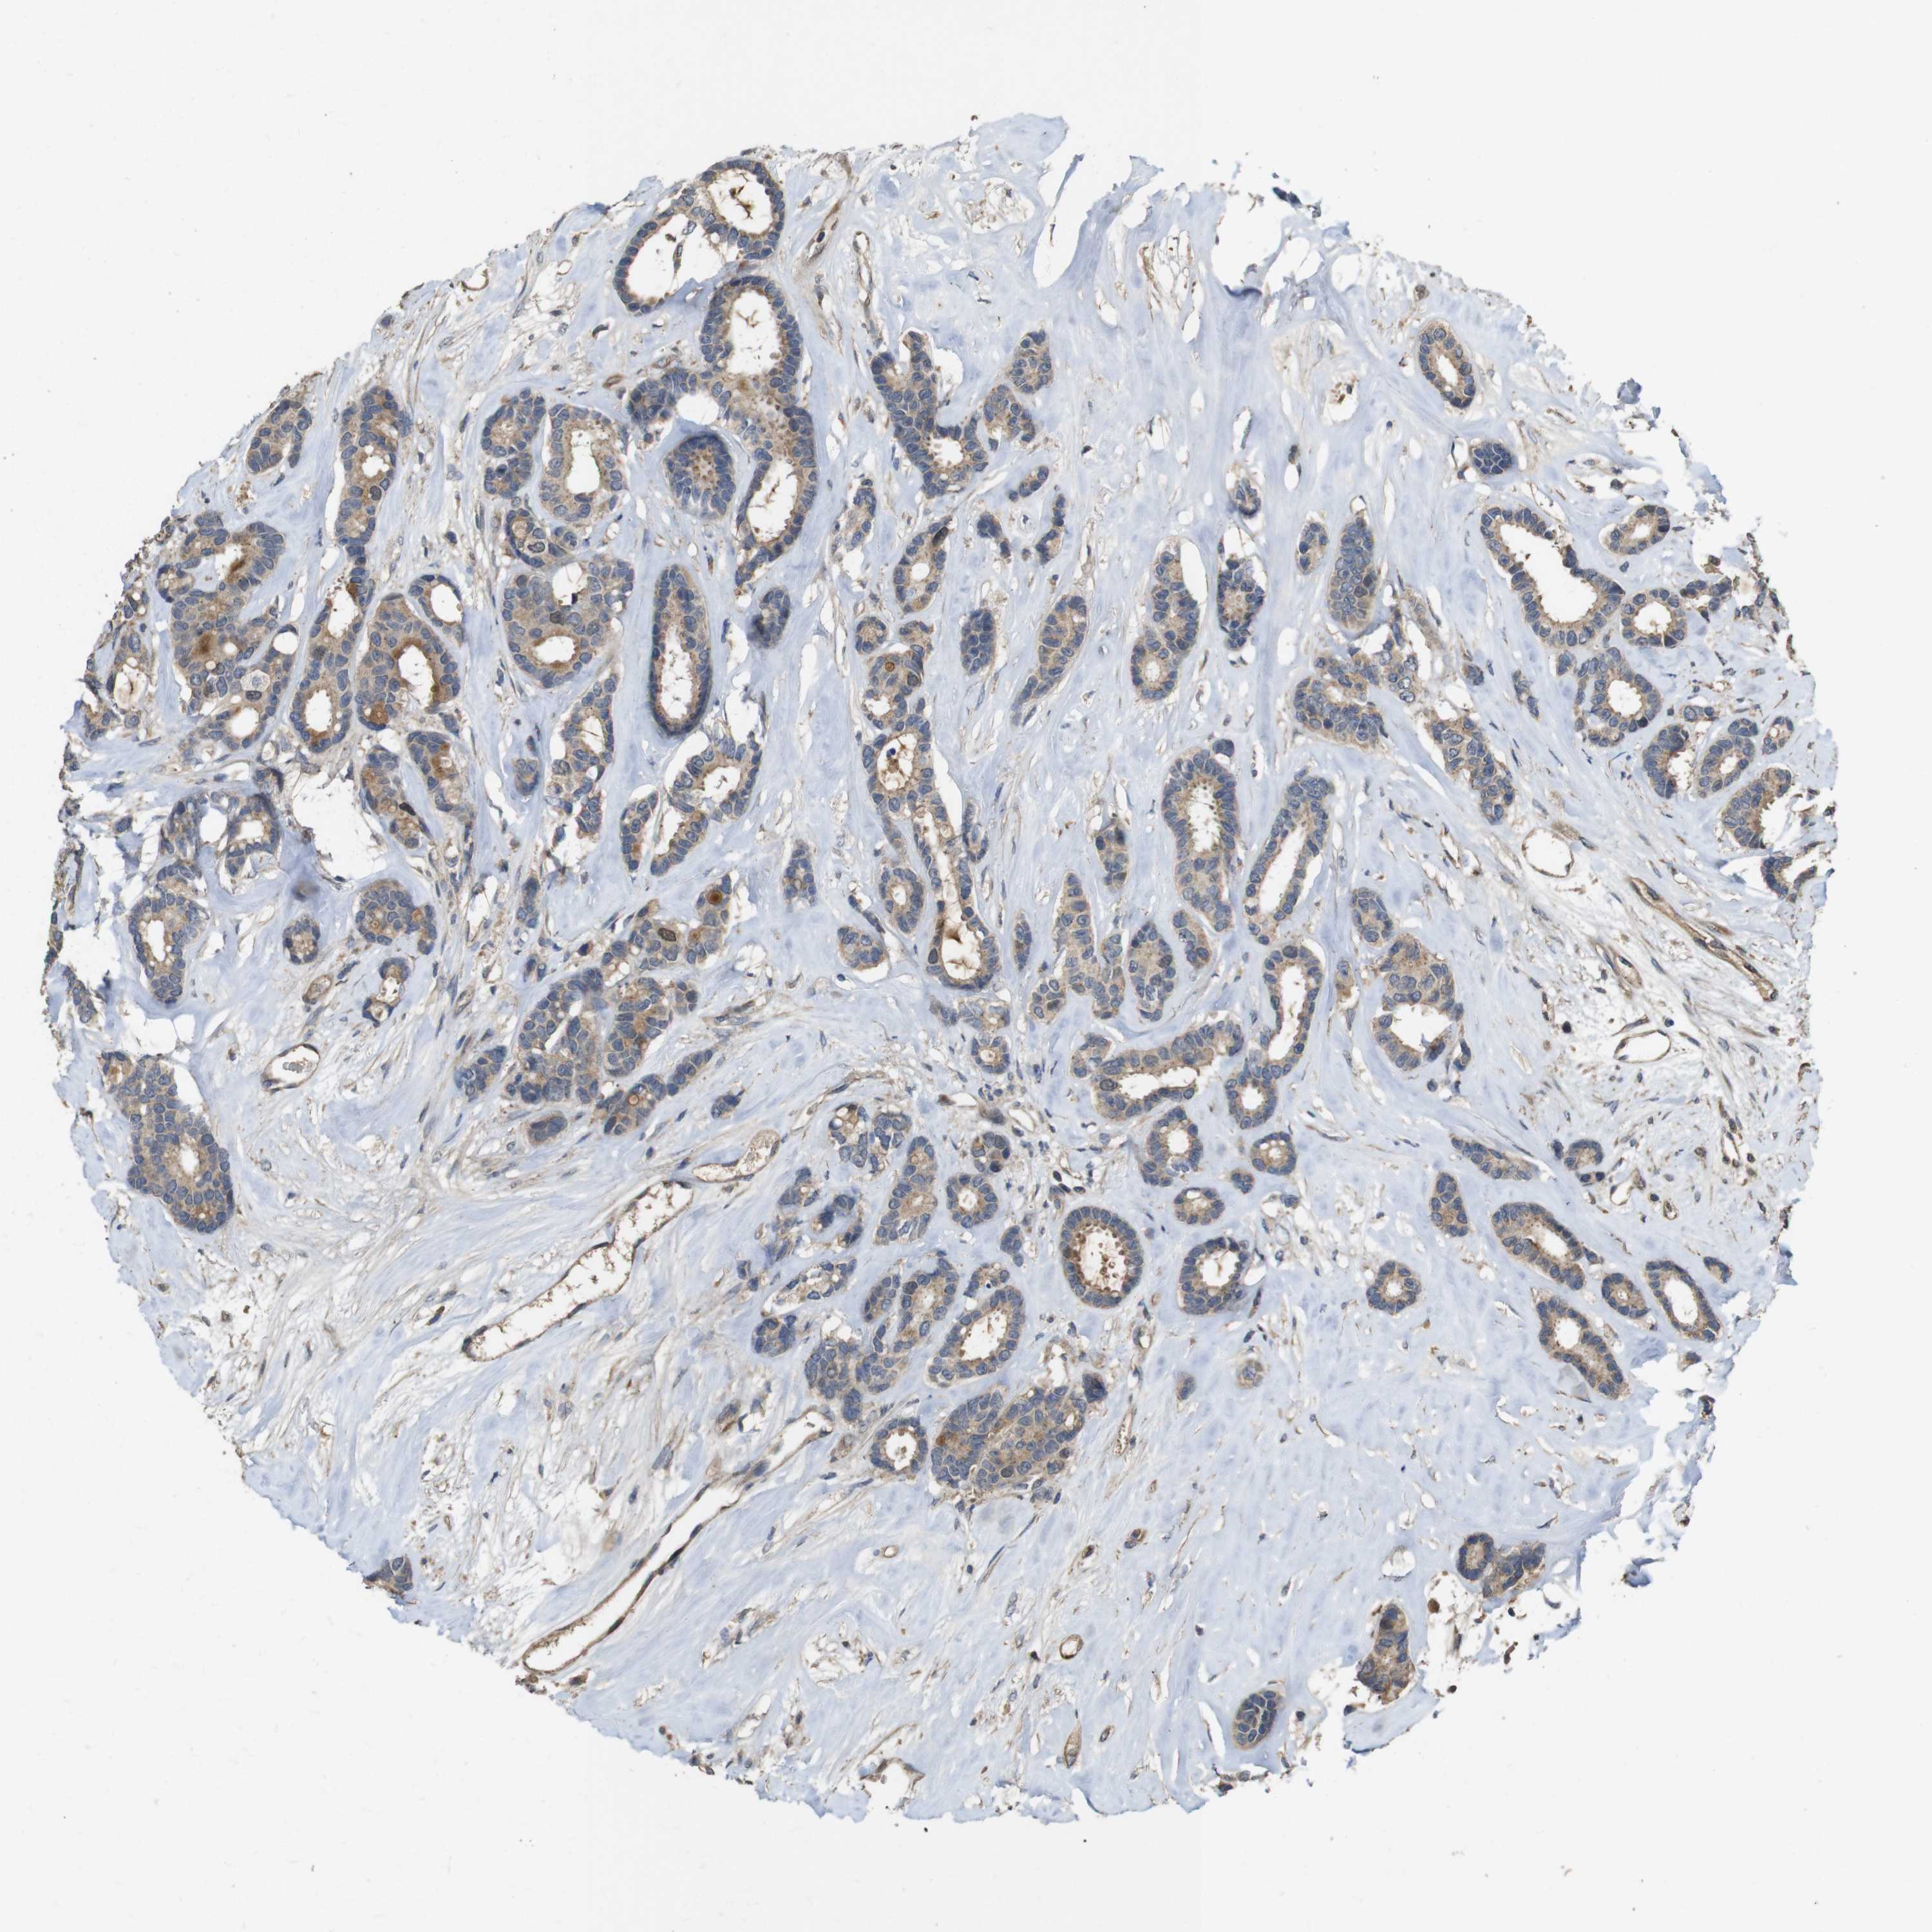

BRCA TCGA BRCA VALIDATION PROTEIN EXPRESSION

ANTIBODIES

AND

VALIDATION